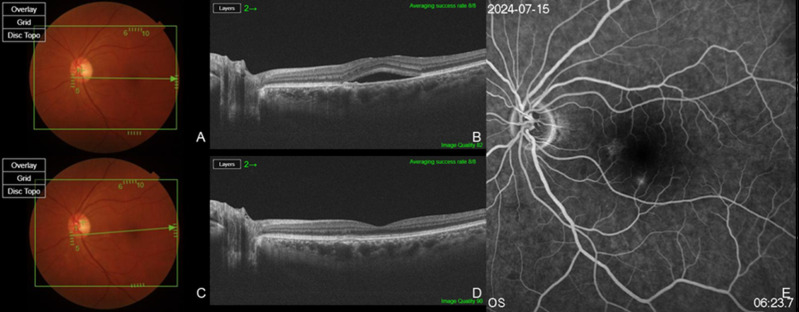

背景/目的:慢性中枢性浆液性脉络膜视网膜病变(cCSC)是一种以持续视网膜下积液(SRF)为特征的视力威胁疾病。虽然存在几种治疗方案,但其疗效各不相同,最佳管理仍不确定。这项回顾性试点研究旨在评估玻璃体内布卢珠单抗治疗无厚脉络膜样血管病(PNV)的症状性cCSC患者的疗效和安全性。方法:对15例无PNV的症状性cCSC患者的15只眼进行单次玻璃体内注射brolucizumab治疗。患者随访6个月。主要结果包括SRF的分辨率和中央亚野厚度(CST)和中央凹下脉络膜厚度(SCT)的变化。最佳矫正视力(BCVA)和眼部安全性也进行了评估。结果:15只眼中有14只眼在6个月内完全消退,占93.3%。平均CST从317.13±73.40µm显著降低至205.53±20.17µm (p < 0.001),平均SCT从475.87±107.66µm显著降低至390.13±121.67µm (p < 0.001)。BCVA改善12眼(80.0%),保持稳定3眼;然而,平均改善(logMAR 0.34±0.33至0.14±0.13)具有统计学意义(p = 0.007)。无明显的眼部不良事件报道。结论:玻璃体内注射brolucizumab可能是降低无PNV的cCSC患者SRF和脉络膜厚度的有效且安全的治疗方法。需要更大规模的对照研究来验证这些发现。

Background/Objectives: Chronic central serous chorioretinopathy (cCSC) is a vision-threatening disorder characterized by persistent subretinal fluid (SRF). While several treatment options exist, their efficacy varies, and optimal management remains uncertain. This retrospective pilot study aimed to evaluate the efficacy and safety of intravitreal brolucizumab in patients with symptomatic cCSC without pachychoroid neovasculopathy (PNV). Methods: In total, 15 eyes of 15 patients diagnosed with symptomatic cCSC without PNV were treated with a single intravitreal injection of brolucizumab. Patients were followed for six months. Primary outcomes included resolution of SRF and changes in central subfield thickness (CST) and subfoveal choroidal thickness (SCT). Best-corrected visual acuity (BCVA) and ocular safety profiles were also assessed. Results: Complete SRF resolution was observed in 14 of 15 eyes (93.3%) within six months. Mean CST significantly decreased from 317.13 ± 73.40 µm to 205.53 ± 20.17 µm (p < 0.001), and mean SCT from 475.87 ± 107.66 µm to 390.13 ± 121.67 µm (p < 0.001). BCVA improved in 12 eyes (80.0%) and remained stable in 3 eyes; however, the mean improvement (logMAR 0.34 ± 0.33 to 0.14 ± 0.13) was statistically significant (p = 0.007). No significant ocular adverse events were reported. Conclusions: Intravitreal brolucizumab may be an effective and safe treatment for reducing SRF and choroidal thickness in patients with cCSC without PNV. Larger, controlled studies are needed to validate these findings.